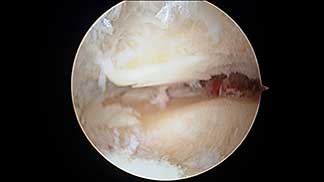

Durante mi entrenamiento en mi segundo fellow en cirugía articular y lesiones deportivas, tuve la oportunidad de hacer una rotación en el hospital CEMA by FIFA (Centro de Excelencia Médica en Altura) en Pachuca Hidalgo, donde brindé atención médica y quirúrgica en las instalaciones de la Universidad a pacientes deportistas profesionales y de alto rendimiento, miembros del equipo de fútbol “Tuzos de Pachuca”.

Galería